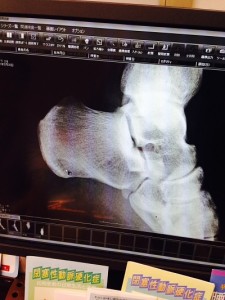

診察の結果、かかとにひびが入っているとの事。